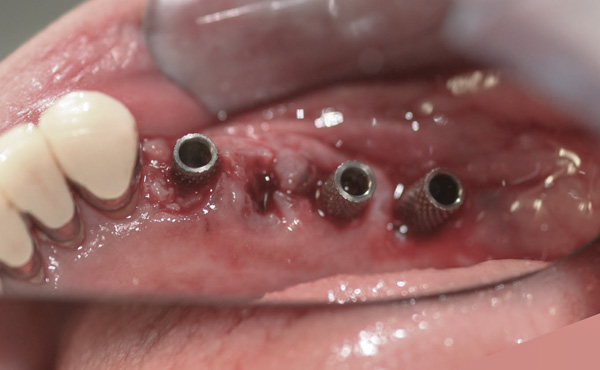

Background: This patient had a failing maxillary dentition and refused to wear a removable prosthesis. A staged approach was employed to retain some of his natural tooth abutments, and recession was noticed at the time of the impression for the second group of implants. Figure 1 shows the patient following insertion of the first set of implant custom abutments; the adjacent natural teeth are still present to support the provisional bridge. Seven months later, as shown in Figure 2, those first-stage custom abutments exhibited evidence of 1 mm to 3 mm of recession.

Results: A decision was made to re-prepare all of the abutments intraorally (Figure 3) so that all abutment margins would be at or below the gingival margin. (Of note, tooth Nos. 8 and 9, also shown in Figure 3, were later submerged for the case to be fully implant-supported.) While re-preparation greatly improved the esthetics of the final result, it required retraction cord placement, new impressions, and new castings.

Figure 2 After 7 months, the first-stage custom abutments exhibited evidence of 1 mm to 3 mm of recession.

Figure 2

Figure 3 Abutments re-prepared intraorally.

Figure 3